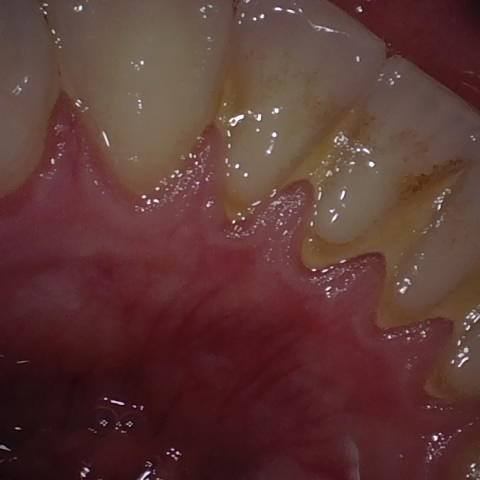

Annotated as "Good"